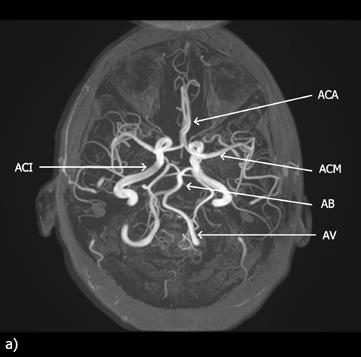

Zásobení mozku okysličenou krví zajišťují čtyři hlavní arteriální zdroje – dvě vnitřní krkavice a dvě páteřní tepny:

• pravá a levá vnitřní krkavice (arteria carotis interna dextra et sinistra) vznikající po rozdělení pravé a levé společné krkavice na zevní a vnitřní větev;

• pravá a levá vertebrální tepna (arteria vertebralis dextra et sinistra).

Levá společná krkavice (arteria carotis communis sinistra) odstupuje přímo z oblouku srdečnice neboli aorty. Pravá společná krkavice (arteria carotis communis dextra) je větví hlavopažního kmene (truncus brachiocephalicus), který se po krátkém průběhu dělí na zmíněnou pravou společnou krkavici a pravou podklíčkovou tepnu (arteria subclavia dextra).

Páteřní tepny jsou větvemi podklíčkových tepen. Pravá páteřní tepna odstupuje logicky z pravé podklíčkové tepny (arteria subclavia dextra) a levá páteřní tepna vychází z levé podklíčkové tepny (arteria subclavia sinistra). Okysličenou krví zásobují mozek, míchu, meningy a hluboké svaly krku.

Obě páteřní tepny se po vstupu do mozkovny spojují v bazilární tepnu (arteria basilaris). Tato tepna je propojena s oběma vnitřními krkavicemi arteriálními spojkami a na spodní straně mozku vytváří Willisův arteriální okruh (circulus arteriosus Willisi), ze kterého odstupují jednotlivé tepny zásobující přední, střední a zadní část mozku.

Odkysličenou krev z mozku odvádějí mozkové žíly (venae cerebri, jednotné číslo vena cerebri) ústící do systému žilních splavů (sinus durae matris). Jejich stěnu tvoří tvrdá plena mozková. Odvádí krev do krčních žil – zejména do vnitřní jugulární žíly (vena jugularis interna).

Žilní splavy jsou vystlány jednovrstevnou výstelkou – endotelem. V jejich stěně nejsou svalové buňky a průtok krve tak nemůže být regulován.

Připomeňme, že do části žilních splavů probíhajících na temeni hlavy (zejména horní sagitální sinus – sinus sagittalis superior) ční výběžky pavučnice (arachnoidální klky –

Pachionské granulace). Právě jejich prostřednictvím jsou do žilní krve odváděny přebytky mozkomíšního moku.

Obr. 2.25 Cévní zásobení mozku – CT angiografie (snímek z vyšetření Jakub Čivrný)

CT angiografie, 3D rekonstrukce v provedení tzv. maximum intensity projection (MIP), frontální pohled.

AB – arteria basilaris, AV – arteria vertebralis, ACI – arteria carotis interna, ACC – arteria carotis communis, Ao – aorta

Obr. 2.26 A + B Willisův okruh – CT a MR angiografie (snímek z vyšetření Jakub Čivrný)

Srovnání MR a CT angiografie. MR angiografie mozku, metoda time-of-flight (TOF), rekonstrukce maximum intensity projection (MIP) (a); CT angiografie mozku, 3D rekonstrukce (b).

ACA – arteria cerebri anterior, ACM – arteria cerebri media, ACI – arteria carotis interna, ACP – arteria cerebri posterior, AB – arteria basilaris, AV – arteria vertebralis